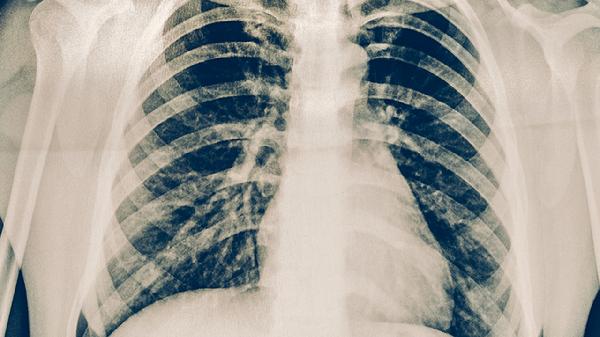

肺结核患者戴口罩近距离会传染吗

肺结核患者戴口罩近距离接触时一般不会传染,但若口罩佩戴不规范或存在破损仍可能传播。肺结核主要通过飞沫传播,规范佩戴口罩可有效降低传染概率。